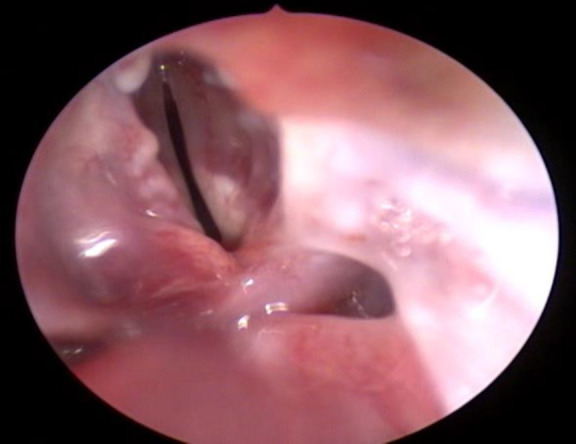

Materials and methods: Ten rabbits were included in this experimental study. A thermal injury was created at the posterior commissure using a conchal probe. Following the injury, one group was treated with mitomycin-C, while the other received epirubicin. After a six-week post-treatment period, the rabbits were euthanized, and both macroscopic and microscopic evaluations were performed to assess stenosis, scarring, granulation tissue, necrosis, and ulceration. Two pathologists, blinded to the treatment groups, independently examined the histological samples.

Results: Macroscopically, no significant differences were observed between the two groups in terms of scarring, synechiae, or granulation tissue formation at the posterior commissure. However, the mitomycin-C group demonstrated a relatively milder tissue response. Microscopic analysis revealed grade 3 collagen deposition in one rabbit and grade 1 in two rabbits from the epirubicin group. In comparison, the mitomycin-C group showed grade 1 deposition in two rabbits and grade 2 in another two. The average fibroblast count was 83.3 in the epirubicin group versus 59 in the mitomycin-C group.